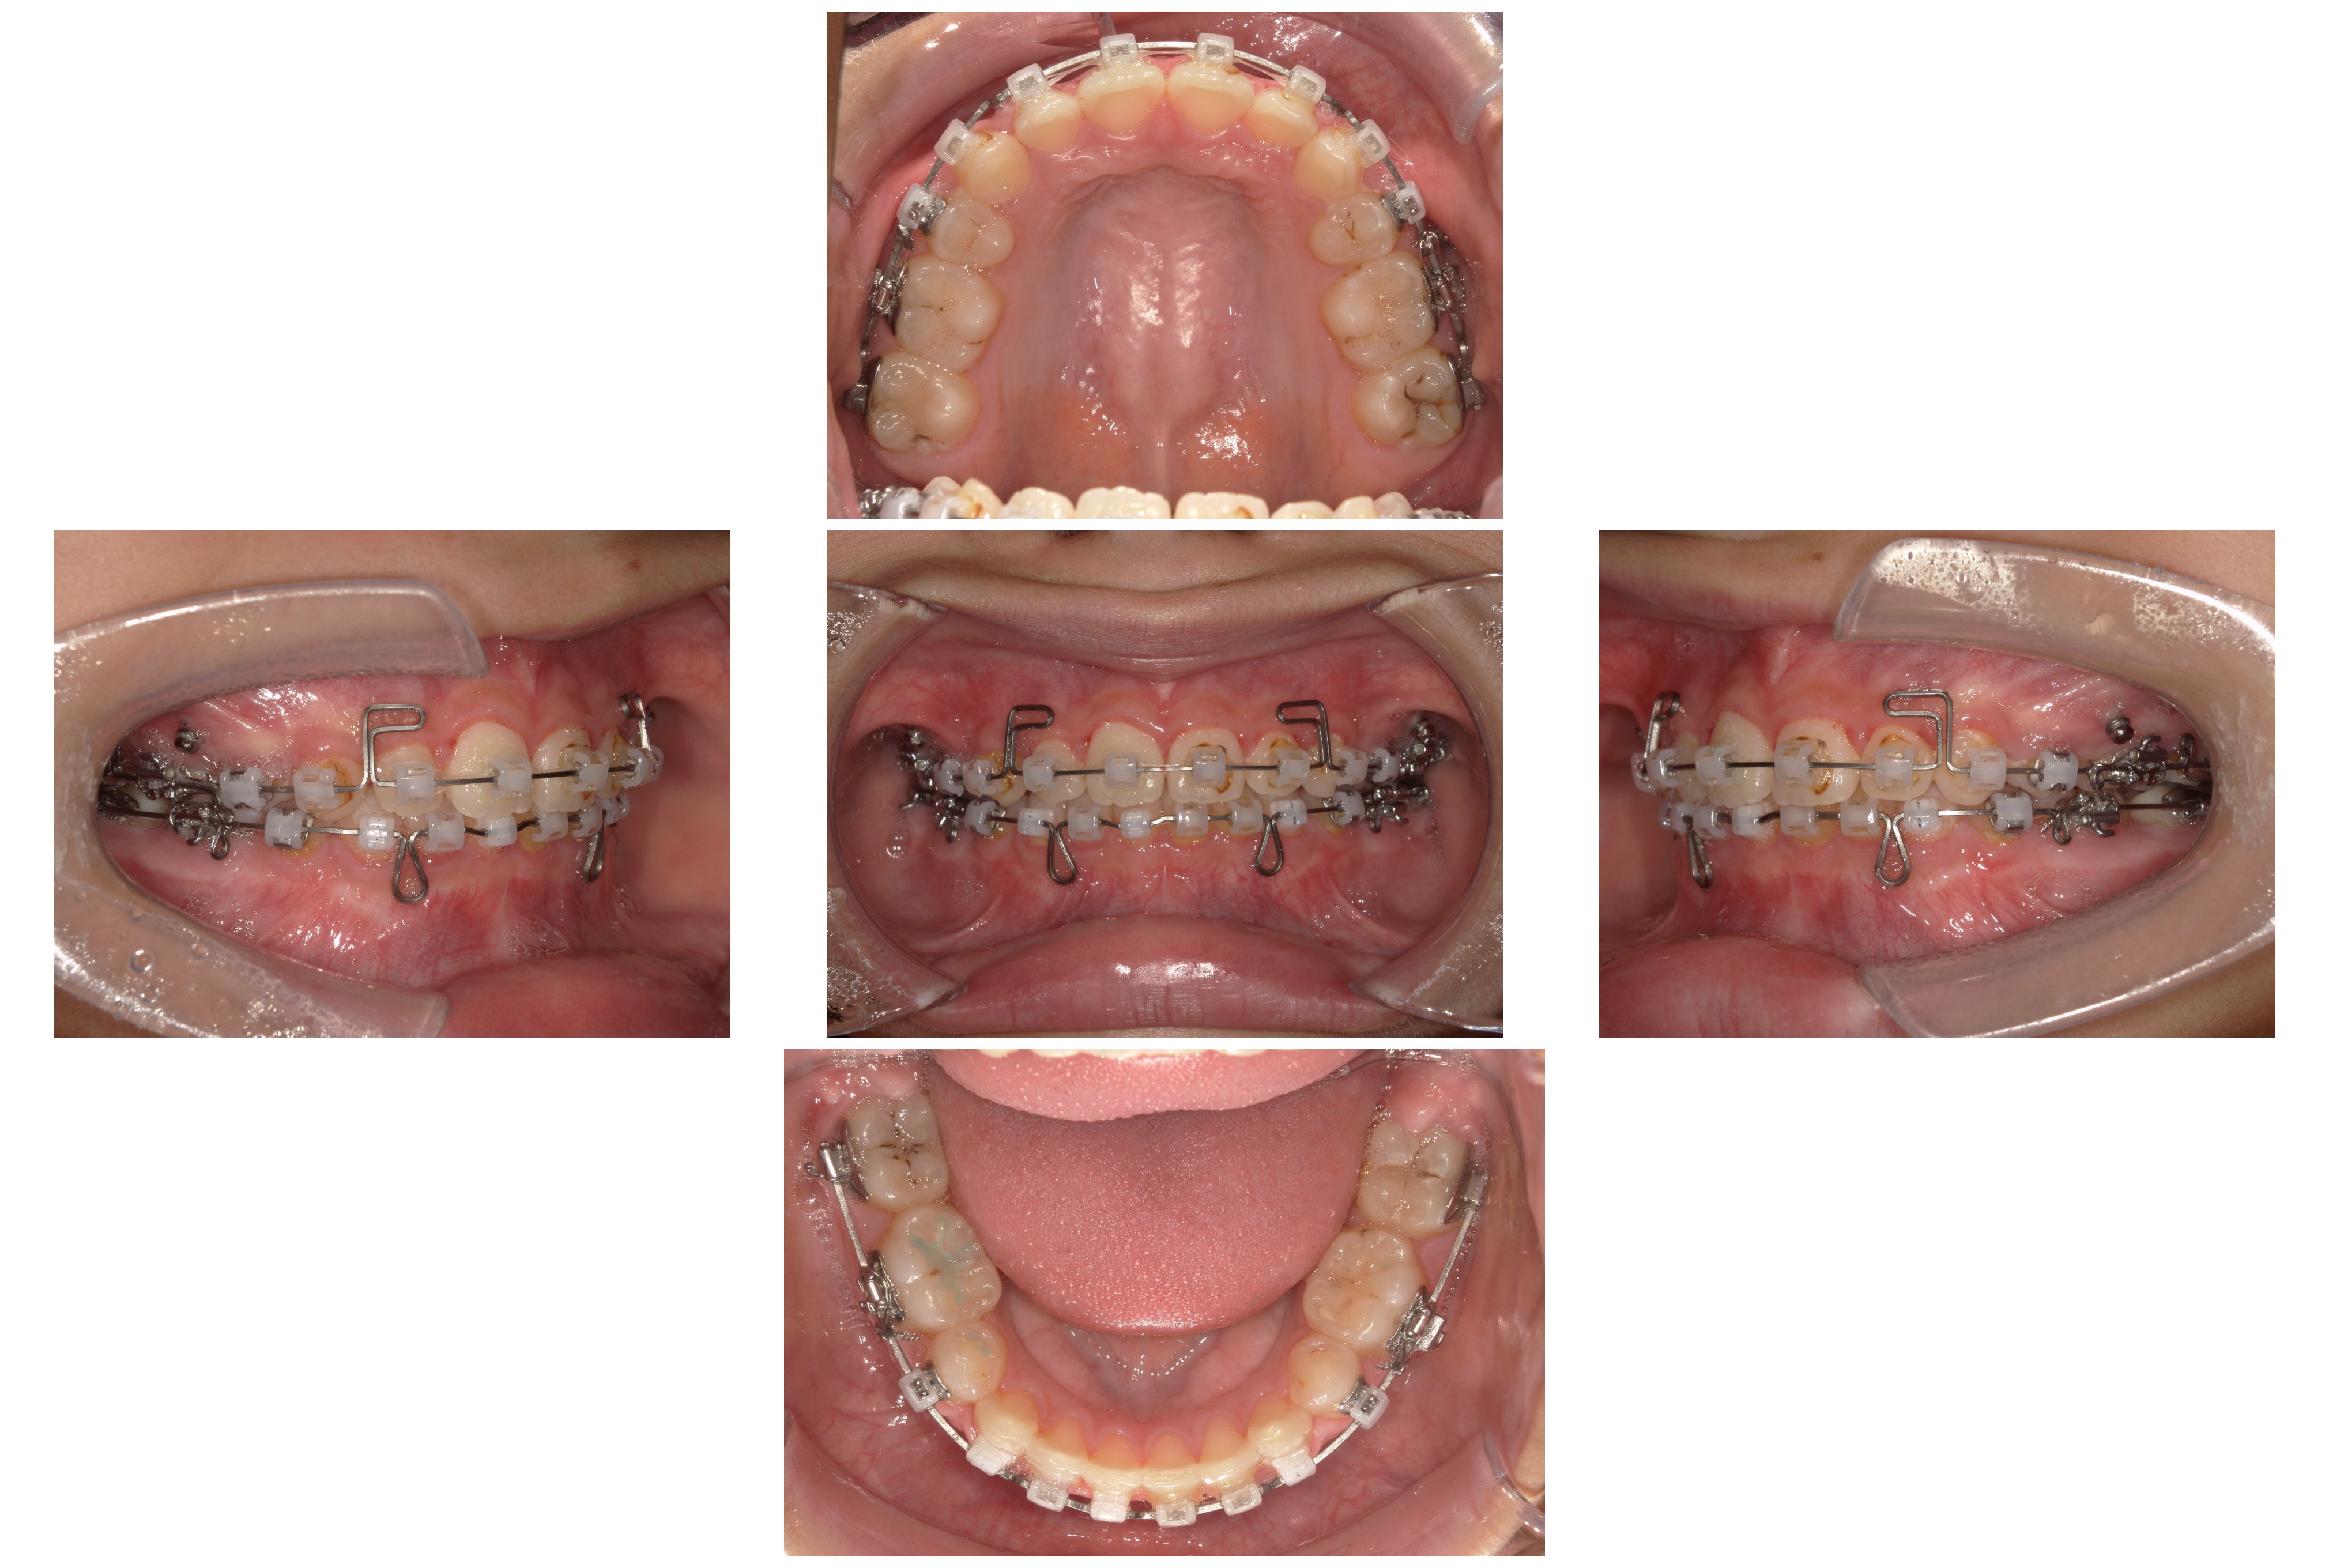

▼2023年8月

④装置装着1年6か月後:スペース閉鎖とエラスティック

「ループメカニクス」というワイヤーの形状を利用して、抜歯したスペースを閉じていきました。この際、患者さんに「エラスティック(矯正用ゴム)」を併用していただくことで、上下の奥歯を理想的な位置関係(Ⅱ級関係の改善)へと導きました。